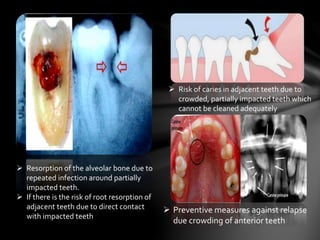

 Risk of caries in adjacent teeth due to

crowded, partially impacted teeth which

cannot be cleaned adequately

 Resorption of the alveolar bone due to

repeated infection around partially

impacted teeth.

 If there is the risk of root resorption of

adjacent teeth due to direct contact

with impacted teeth

 Preventive measures against relapse

due crowding of anterior teeth